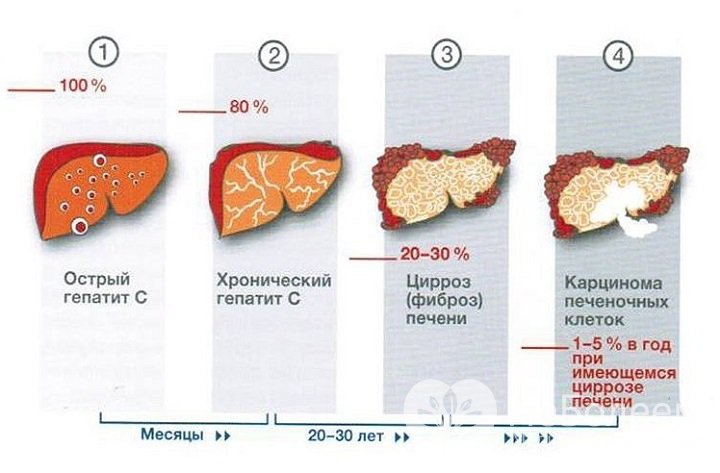

Признаки заболеваний печени: Важные симптомы и рекомендации